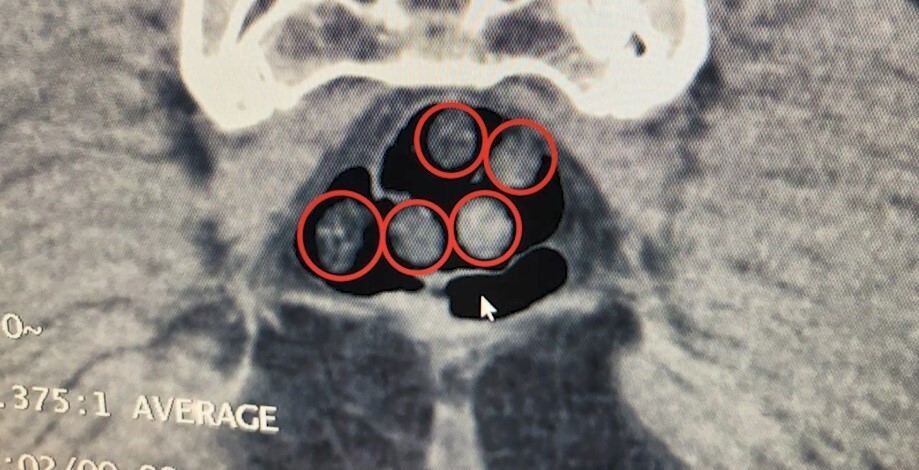

Aynı yerde, yolcu olarak seyahat eden yabancı uyruklu iki şahıs da gözaltına alındı. Tatvan Devlet Hastanesi'nde yapılan röntgen ve tomografi incelemelerinde, şahısların mide ve bağırsaklarında çok sayıda yabancı cisim tespit edildi. Yapılan tıbbi müdahale sonrası, bu şahısların yuttuğu toplam 50 kapsül, 385 gram metamfetamin ele geçirildi.

TATVAN DEVLET HASTANESİNDE YAPILAN RÖNTGEN VE TOMOGRAFİ İNCELEMELERİNDE, ŞAHISLARIN MİDE İLE...